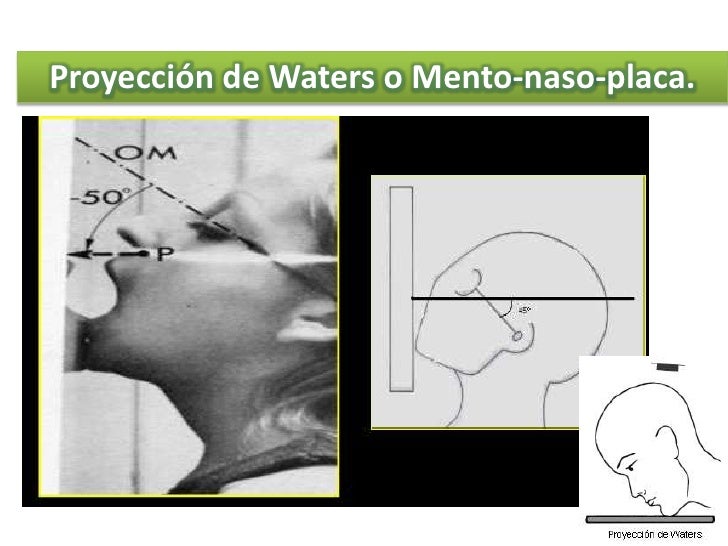

Download scientific diagram | Radiografía simple de cráneo en proyección de Waters, en la que se aprecia densidad aire en la órbita superior izquierda (Caso 2). from publication: Enfisema.

HUESOS PROPIOS DE LA NARIZ. PERFILOGRAMA (LATERAL) WATERS. ANTERO POSTERIOR (AP) PERFILOGRAFÍA (WATERS Y LATERAL) PERFILOGRAFÍA CON AP (WATERS, LATERAL Y AP) Para consultar precios y realizar cita, cóntactanos a los teléfonos. 55 58 19 15 59 y 55 20 75 47 97.

Radiología Tecnica de Waters - Descargar como PDF o ver en línea de forma gratuita. Proyeccion ap, lateral y oblicua del pie HillaryPerez7. Forma parte de serie radiográfica para evaluación de senos paranasales, junto a RX Caldwell y lateral de cráneo 4. La proyección de water es muy útil para estudiar el piso de la órbita,.

El estudio de "Rx Senos Paranasales 3 Proyecciones (Waters, Caldwell y Lateral)" implica la captura de imágenes radiográficas de los senos paranasales desde tres direcciones diferentes utilizando las técnicas de Waters, Caldwell y lateral. 1. **Técnica Waters**: En esta proyección, el paciente se coloca de pie o sentado con la cabeza.

Estudio de la identificación de las distintas estructuras que podemos describir en una Rx de cráneo (water)

Waters view Radiology imaging, Radiology, X ray

El estudio de "Rx Senos Paranasales 1 Proyección (Waters, Caldwell o Lateral)" implica la toma de una radiografía de los senos paranasales desde una sola dirección utilizando una de las siguientes técnicas: Waters, Caldwell o lateral. 1. **Técnica Waters**: En esta proyección, el paciente se coloca de pie o sentado con la cabeza.

La opción ideal en la sospecha de cualquier traumatismo craneofacial es la TC. En caso de no disponer de tomografía, las proyecciones de radiología convencional más apropiadas en estas situaciones son: el Waters (occipitomental), la proyección de Caldwell (occipitofrontal), la lateral y la proyección de Hirtz o de arcos cigomáticos.

grupos de senos. Proyección PA axial (Método Cadwell): Senos frontales y etmoidales anteriores. Proyección de Waters (Parietoacantial): con boca cerrada: Senos maxilares Proyección de Waters (Parietoacantial) con boca abierta: Senos maxilares y esfenoidales. Proyección Submentovertical: Senos etmoidal y esfenoidal. Centraje: Línea.

Proyección de Caldwell: proyección AP de los senos paranasales en flexión de la cabeza, placa entre. Proyeccion lateral: imagen del plano sagital del paciente. 3. Indicación. -Trauma facial. -Actualmente la radiografía simple de cavidades paranasales no se recomienda para el estudio de sinusitis aguda, ya que su diagnóstico es clínico. 4.